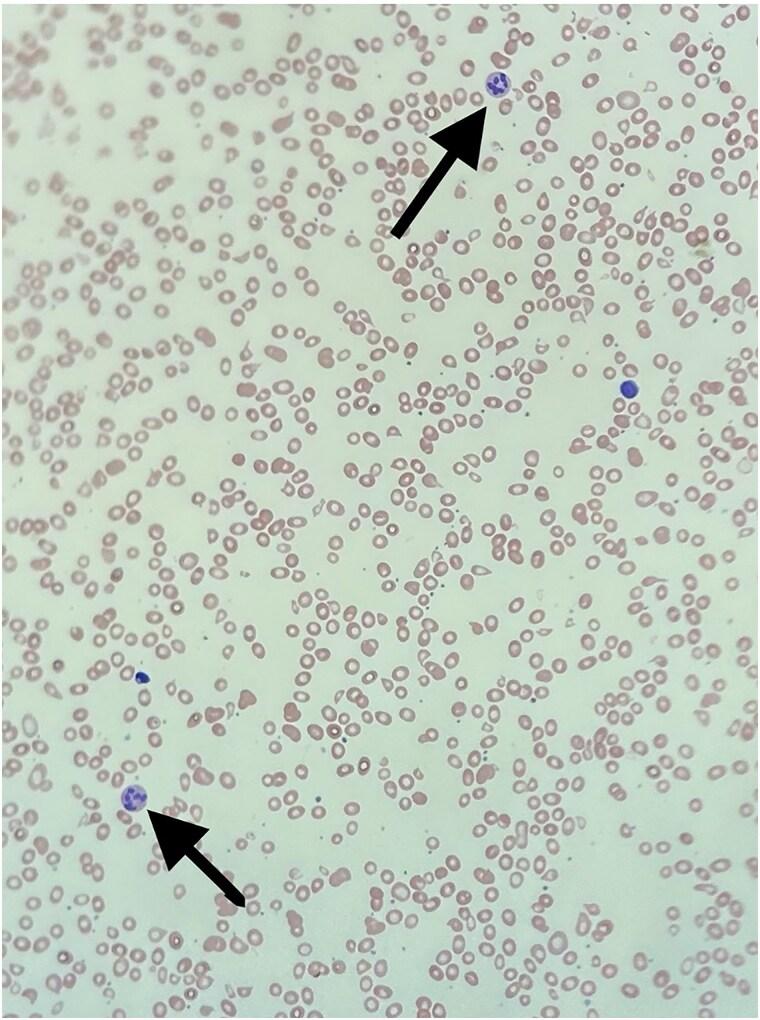

Autoimmune polyendocrinopathy-candidiasis-ectodermal dystrophy (APECED) is an autosomal recessive disease caused by a monogenic pathogenic mutation in the autoimmune regulator () gene. is a transcriptional regulatory gene expressed within thymic medullary cells, which play a critical role in developing central immune tolerance. APECED is classically associated with the triad of chronic mucocutaneous candidiasis, hypoparathyroidism, and adrenal insufficiency. We report a case of a pediatric patient with a known history of APECED who presented with symptomatic megaloblastic anemia and was found to have vitamin B12 deficiency secondary to the presence of antibodies to intrinsic factors. Interestingly, our patient did not have gastric parietal cell antibodies, which are present in 90% of pernicious anemia cases. Pernicious anemia itself is relatively rare and primarily manifests in the elderly population. There is limited literature involving pernicious anemia within the pediatric population, specifically within the subgroup that has APECED. Screening and early recognition of pernicious anemia in this relatively rare condition is crucial, as it has the potential to be life-threatening if left unaddressed.

摘要